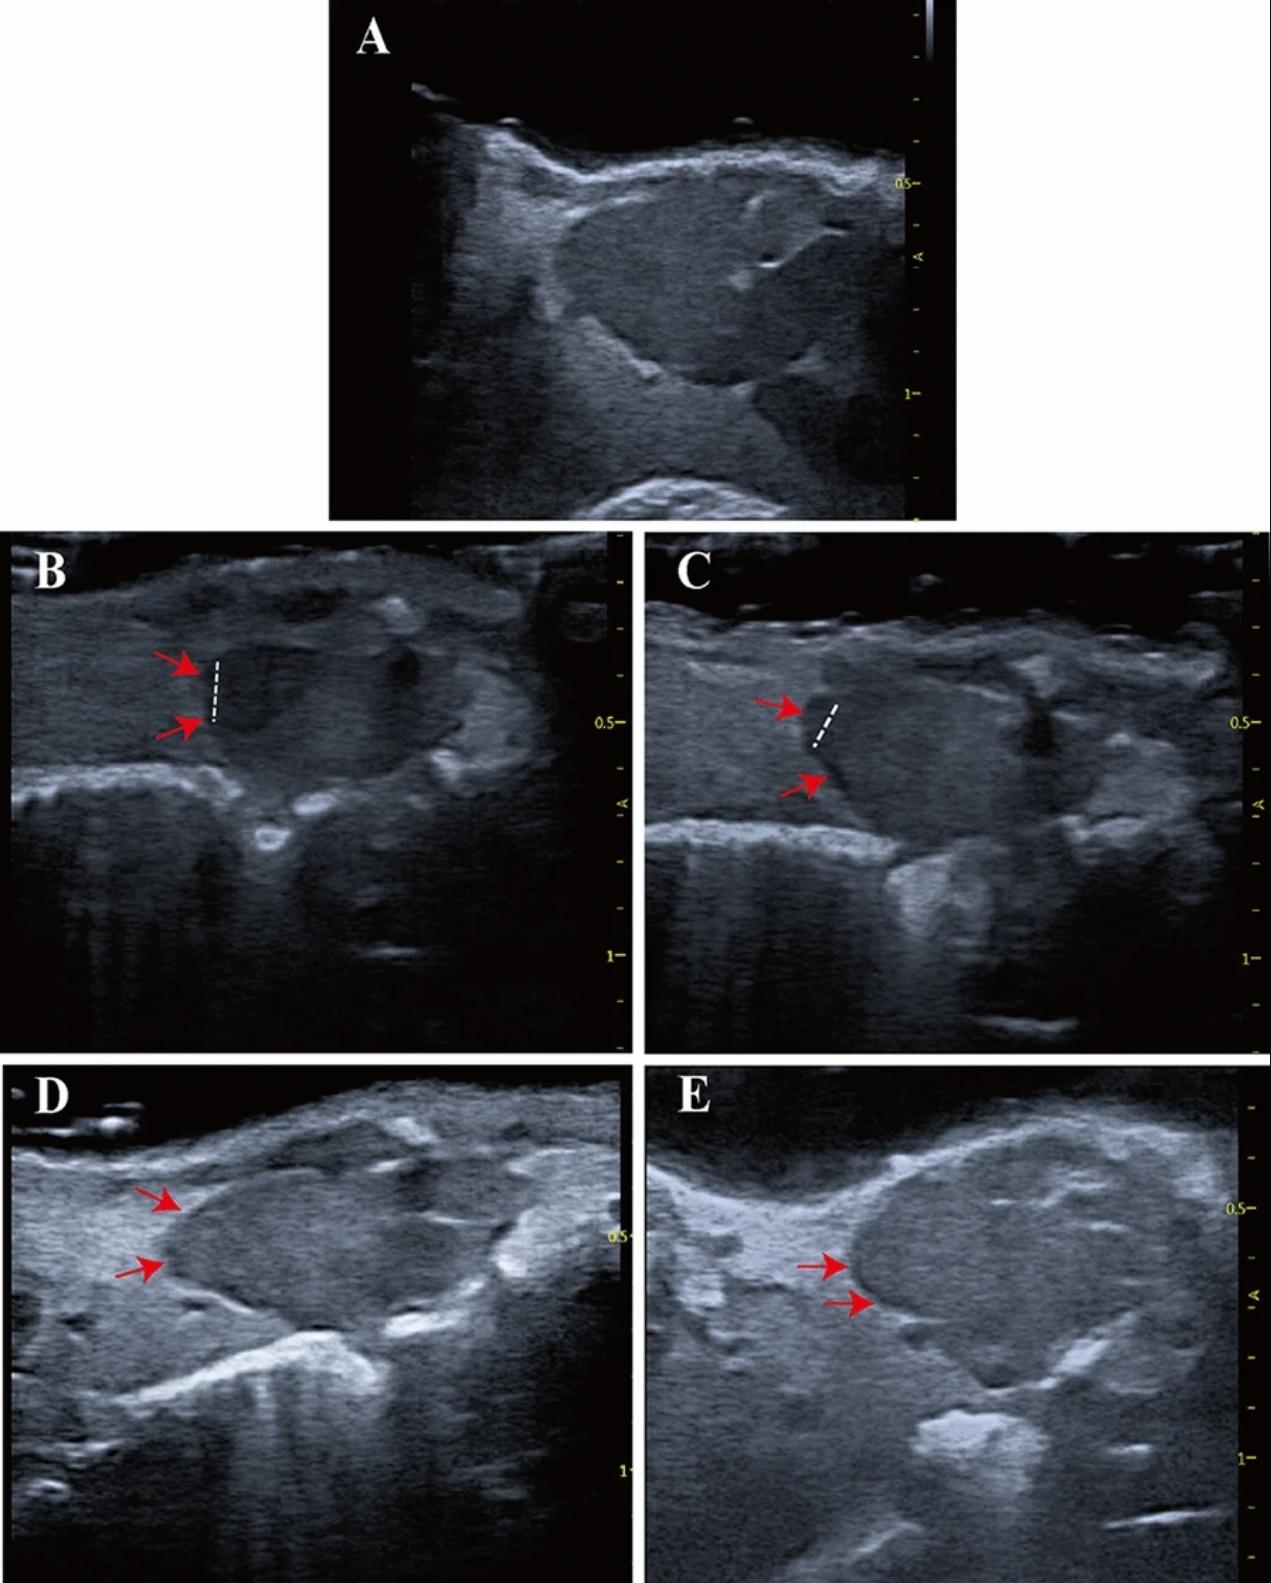

Fig. 5 Echocardiographic imaging can monitor nonperfect regeneration with the adhesion of X. tropicalis injured hearts. A: Representative echocardiography image of the same-age nonapical resection group under B-mode. B: Representative echocardiographic image of the injured heart at 5 daar, in which adhesion was identified at the boundary between the apical region of the regenerated heart and the surrounding tissue. C: Representative echocardiographic image of the injured heart at 10 daar, in which adhesion was identified at the boundary between the apical region of the regenerated heart and the surrounding tissue. D: Representative echocardiographic image of an injured heart at 30 daar, in which adhesion was identified at the boundary between the apical region of the regenerated heart and the surrounding tissue. E: Representative echocardiographic image of the injured heart at 45 daar, in which adhesion was identified at the boundary between the apical region of the regenerated heart and the surrounding tissue. Yellow arrow: The adhesion between the apical region of the regenerated heart and the surrounding tissue. F: Ex vivo gross observation of the regenerated X. tropicalis heart at 45 daar, in which echocardiography observation showed that the injured heart was regenerated with nonperfect regeneration with adhesion. F-f1: Representative image of the regenerated X. tropicalis heart at 45 daar after in vivo exposure. White arrow: Adhesion tissue. F-f2: Front side image of the isolated heart of F-f1. F-f3: Image of the dorsal side of the isolated heart of F-f1. F-f4: Apical side image of the isolated heart of F-f1. Black arrow: A defect after the adhesion tissue was cleaned during heart isolation. Ex vivo gross observation confirmed that the cut apex was regenerated in a nonperfect manner with adhesion, in which the boundary between the apical region of the regenerated heart and the surrounding tissue was connected to adhesion tissue. 5 daar: 5 days after apical resection